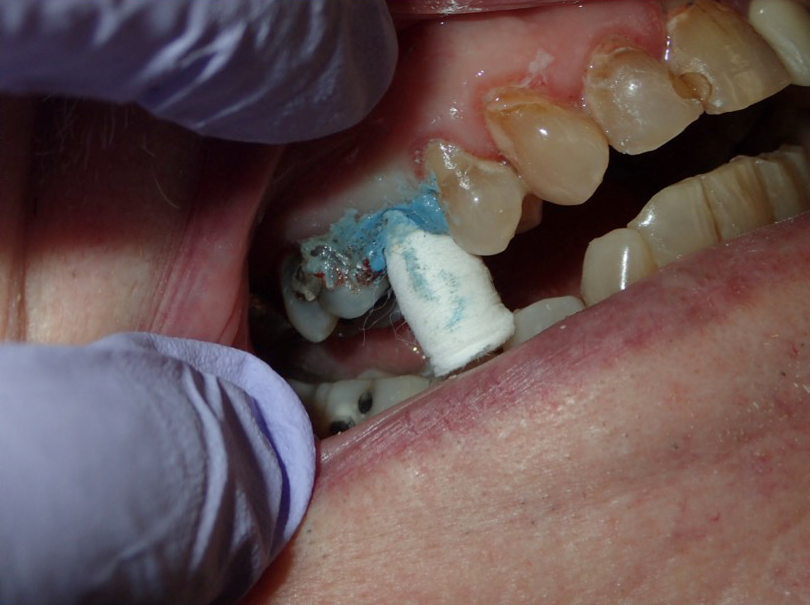

Fig 3. Retraction cord being packed.

Figure 3

Fig 8. Cotton retraction cap in place.

Figure 8

An advantage of using cord technique is that it generally provides an accurate and precise measurement,7,8 physically separating the gingiva away from the prepared margin to allow the clinician to insert light-body material to flow below the margin. Additionally, if a double-cord technique is used, the clinician can leave the bottom cord in place. Moreover, no new equipment is required, and chemicals may not be needed. The clinician needs only the cord and a cord packing instrument. Drawbacks to using cord are the risk of epithelial attachment injury, some pain that may necessitate the use of local anesthesia, a level of technique sensitivity that typically requires practice on the part of the clinician to become skilled, the likelihood of bleeding, and the risk of irreversible gingival injury that may lead to permanent recession.9,10 Figure 2 through Figure 5 show close-up photographs of a prepared tooth and margin, cord being packed, cord in place, and margin after cord removal, respectively.

Figure 6 through Figure 9 demonstrate the use of retraction paste and a cap. An upper bicuspid was prepared (Figure 6), and some bleeding occurred due to the clinician working below the existing restorations. Retraction paste was then applied (Figure 7), but there was still some residual bleeding. The clinician then had the patient close on the retraction cap to stop the bleeding (Figure 8). Some blanching occurred as the patient bit into the cap. The patient will hold that position depending on how much bleeding occurs. Figure 9 shows the exposed margin ready for impressioning. In this case, the retraction cap was kept in place with the patient biting down on it for 2 to 3 minutes instead of 1 to 2 minutes because there was a fair amount of bleeding initially.